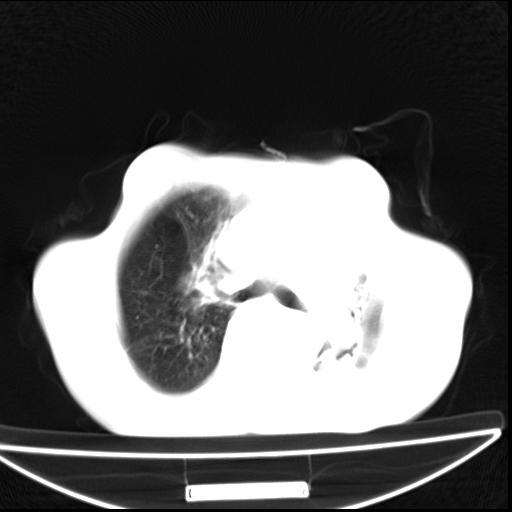

男  70岁,发烧咳嗽4天。盗汗,消瘦。无痰中带血丝,以前有肺tb病史,ct见,双肺tb,左侧胸廓塌陷,左胸膜肥厚粘连。纵隔移位,右侧胸腔积液,大家说说那个心影前左肺舌叶除了肺大炮还有炎症还是干酪性肺炎?有占位吗?我看纵隔淋巴结也大。

双肺继发性肺结核伴部分左肺毁损!

1)两肺继发性肺结核并左肺上叶肺不张,支气管扩张。2)双侧胸膜炎(胸膜增厚+少量胸腔积液)。